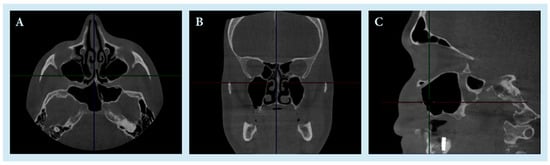

Fungal Sinusitis Masquerading as Trigeminal Neuralgia in an Immunocompetent Patient: A Case Report

Previous cases of trigeminal neuralgia (TN) caused by fungal sinusitis have been reported, but mainly in immunocompromised patients. We present a case of fungal sinusitis masquerading as trigeminal neuralgia in an immunocompetent patient and discuss the potential implications of these two diseases. The patient is a 59-year-old male who presented with a four-year duration of left facial pain. He had been diagnosed and treated for trigeminal neuralgia by a pain specialist but was subsequently referred to ENT after a MRI of the brain showed left maxillary sinusitis. Nasoendoscopy findings and a CT scan of the paranasal sinuses were concordant with left maxillary sinusitis. The patient underwent left functional endoscopic sinus surgery and recovered uneventfully. Our study shows that even in immunocompetent patients who present with non-resolving or worsening facial pain resembling the original diagnosis of TN, clinicians should remain vigilant for the possibility of alternative underlying pathologies including fungal sinusitis. Full article